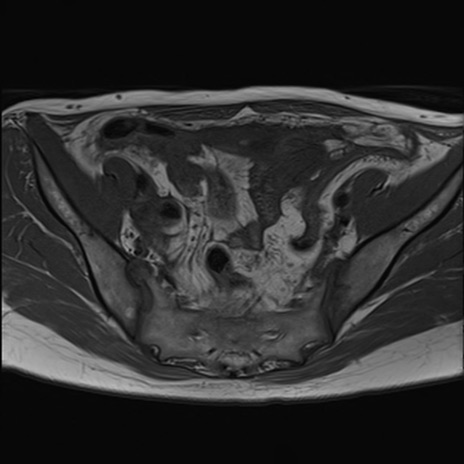

症例39 T1WI(横断像)

MRI(4日後)